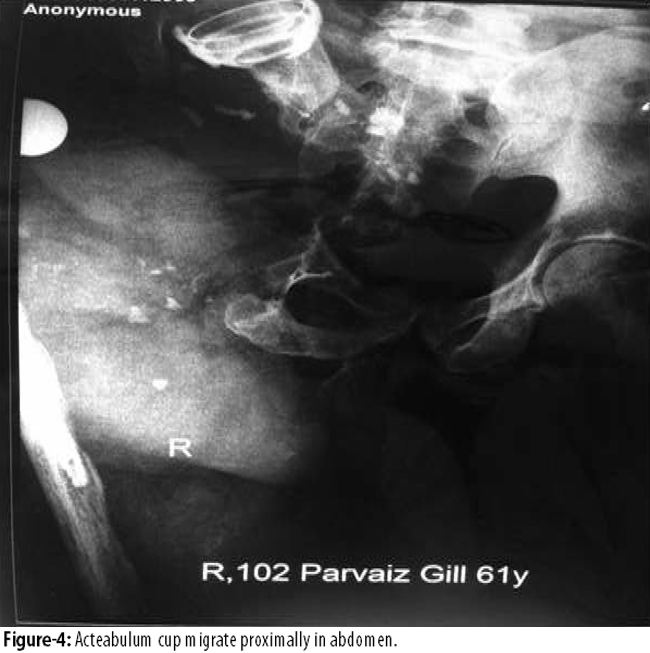

and cup was placed at the lower abdomen (Figure-4).